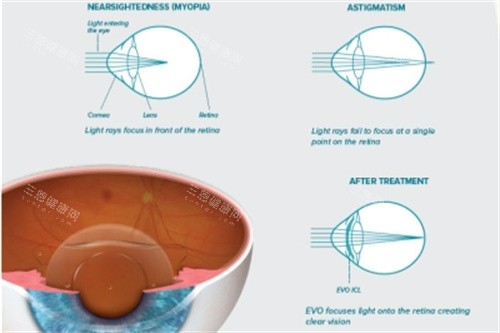

"近视十年,镜片比瓶底还厚!""戴隐形眼干到想抠眼睛!""激光手术怕后遗症?"——这些吐槽是不是你的日常?当传统近视手术还在"削角膜"时,ICL晶体植入术已经杀出重围,用一枚比头发丝还薄的"隐形眼镜",让高度近视党也能体验"摘镜自由"。更绝的是,全程只需10分钟,3mm切口就能完成!今天咱们就扒开这层"神秘面纱",看看医生在手术室里到底干了啥?

"您这角膜厚度不够,做不了激光。"——这句话是多少高度近视者的噩梦?ICL的独特之处,就在于它不"动刀"角膜,而是往眼睛里"装"一枚人工晶体。但别以为这就能随便做,术前检查堪称"闯关游戏":

用IOLMaster测眼轴长度,OCT扫黄斑区,UBM查前房深度——这些科技设备就像给眼睛做"CT",精细到0.01毫米。上海五官科医院陈主管强调:"前房深度<2.8mm的,装晶体可能引发青光眼!"